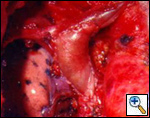

The anatomy of the SVC (Figure 1) and left brachiocephalic vein put this venous system in a critical area vulnerable to tumors arising both in the lung and anterior mediastinum. Malignant invasion is the most frequent indication for SVC resection and reconstruction. Lung cancer can involve the vessel with direct invasion by primary tumors arising in the right upper lobe or by nodal metastases (stations R2, R4 and 3) (Figure 2). Anterior mediastinal tumors (thymoma, thymic carcinoma, germ cell tumors, etc) may involve directly both the SVC and the left brachiocephalic vein (Figure 3). Primary tumors of the SVC represent a rare indication for surgery. Other infrequent indications are saccular aneurysms or primary malformations and traumatic lesions (iatrogenic, blunt, or penetrating injuries).

| Figure 2A & B. (A) Lung cancer invading the superior vena cava. (B) Mediastinal lymph nodes invading the superior vena cava. | Figure 3. Cortical thymoma invading the superior vena cava. | |